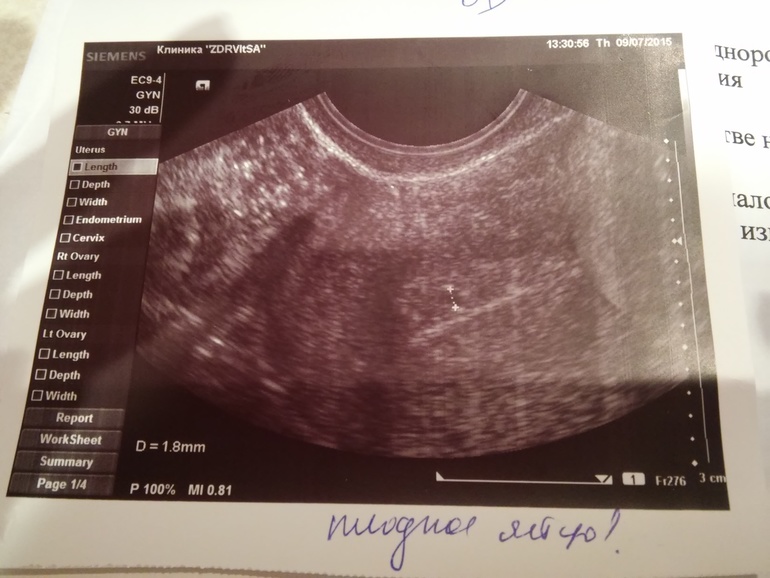

Вот уже 39 дц...месячных нет.. Я снова проснулась с ужасным чувством тошноты.. Видимо от таблеток(( Постоянно закрадывается мысль, о моей беременности.. Не могу понять как можно было увидеть плодное яйцо,а беременность не подтвердить?..((